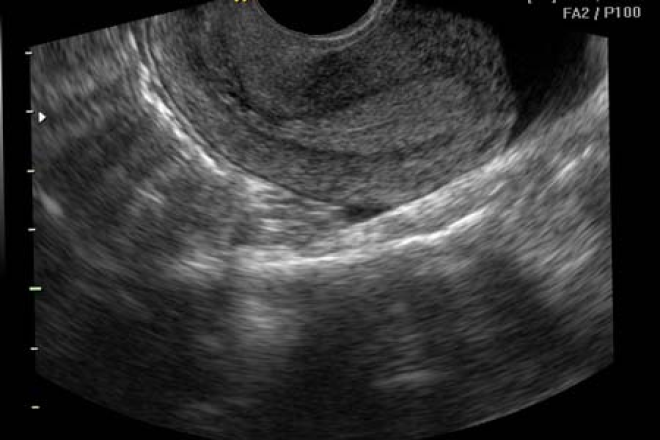

El endometrio ocupa el centro del útero y constituye la mucosa de la cavidad uterina. Su forma triangular es evidente en la vista coronal (frontal).

Es crucial tener en cuenta la posición del útero, ya sea en anteversión o retroversión, para orientar el transductor de forma adecuada en planos coronales o transversales.

Para estudiar los ovarios, se comienza identificando el útero en un plano sagital y se ubica el haz del ultrasonido en el fondo uterino. Posteriormente, se gira el transductor para obtener un corte transversal o coronal que muestre la imagen característica de los ovarios, con ecogenicidad similar a la del útero. Luego se procede a medir los diámetros, pudiendo hacerlo vía abdominal o intracavitaria.